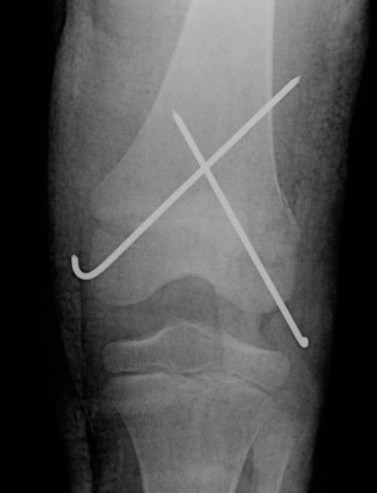

Distal Femoral Fracture SH2 APDistal Femoral Fracture SH2 Lateral

Salter Harris Type II